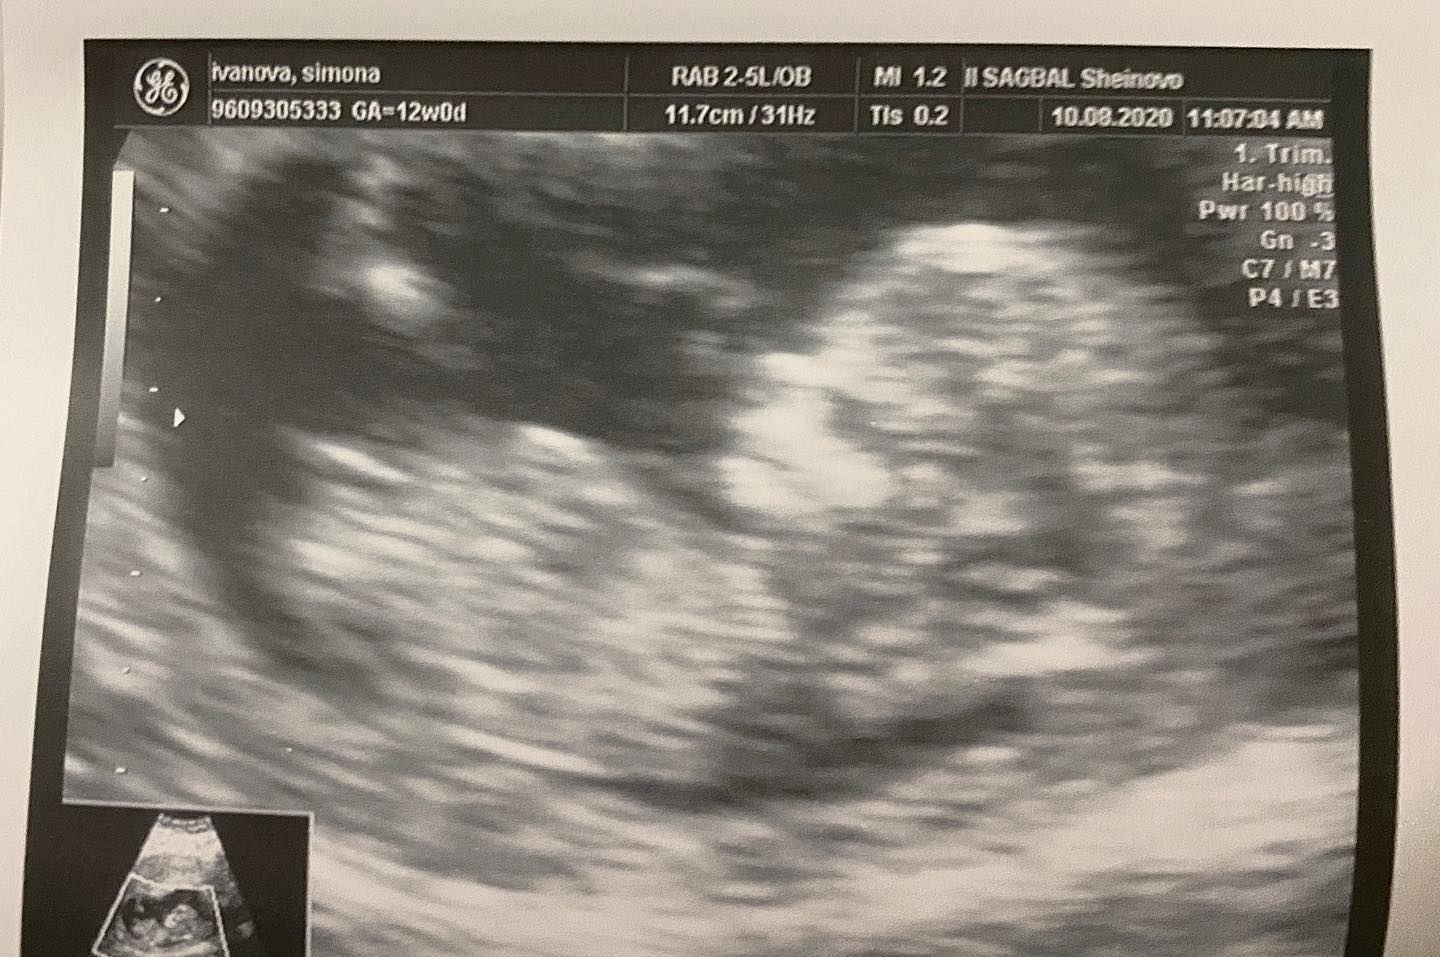

С началото на новата година тя реши да повдигне още повече завесата и да покаже снимка от видеозона, която толкова много разчувствала нея и приятелят й Даниел Милушев.

„Благодаря на Бог за това, че гледам смело напред и с надежда за всичко хубаво, което ни предстои! Вярвам, че тази година ще ни донесе много радост и усмивки! Бъдете здрави! Бъдете щастливи! Мечтайте! Вярвайте в чудесата! Грижете се за близките си! Напомняйте им колко са важни за вас! Постигнете целите си! Нека новата година бъде по-добра за всички ни! Обичайте се“, написа дъщерята на Глория в социалните мрежи и пусна първата снимка на бебето си, което ще се пяови ан бял свят до броени дни.